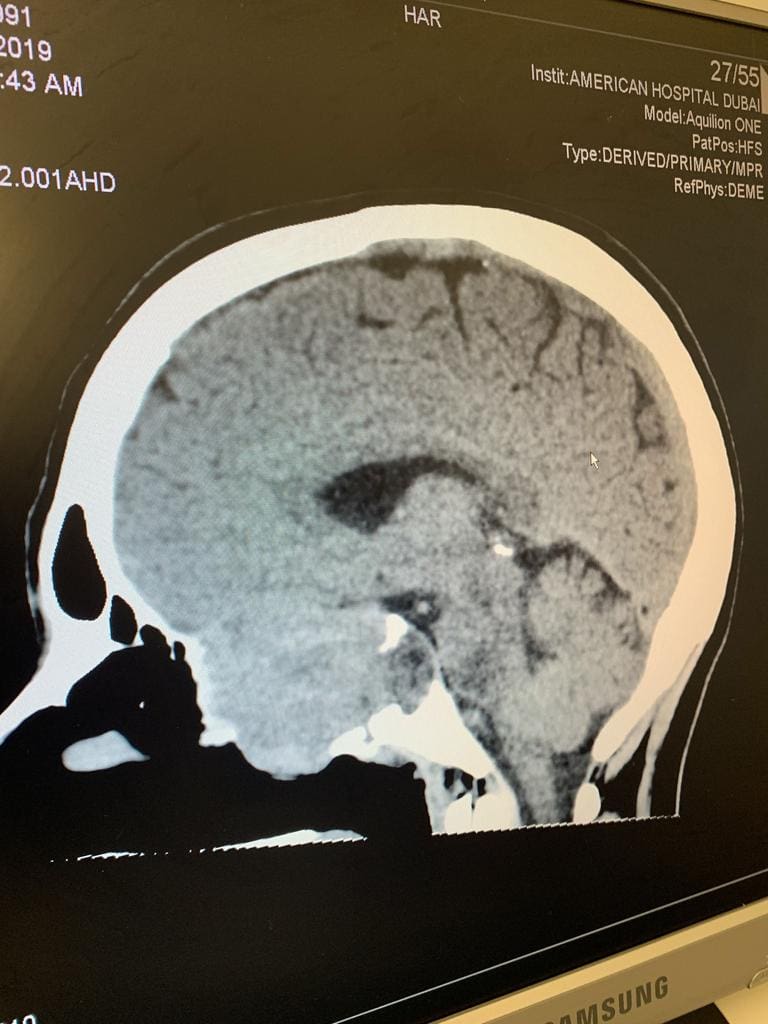

Then headaches and sinusitis symptoms were dismissed as such – until Lahey started losing vision from her left eye. Scans showed a cricket ball-sized mass in her sinus skull bone, and a diagnosis of NUT carcinoma, with a six-to-nine-month survival rate. About 100 people are diagnosed with the rare cancer every year. It’s hard to test for and diagnose, it doesn’t respond well to standardised treatments. There is no cure.

Recently, however, it was discovered the cancer had spread to her brain. Doctors cannot tell how long she has.

“I’ve had some regrowth of my primary tumour in that time, and also metastasis to the brain ... so I guess that falls back into my belief into cancer research, because without things like genomic testing, targeted treatments and support for people with rare cancers, I wouldn’t be here. I’m proof that it works.

Today, like most days, Lahey feels as well as she can feel. The vision in her left eye never returned, presenting new challenges. She gets scans every three months to monitor the cancer that metastasised on her brain. She’s never out of the woods, just in the limbo of “scanxiety” that every 60 days determine her fate.